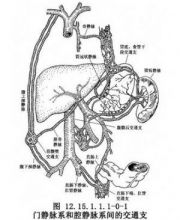

| 2021年7月26日 (一) 20:01 | 门静脉解剖.jpg (文件) |  |

36 KB | 77921020 | Uploaded with SimpleBatchUpload | 3 |